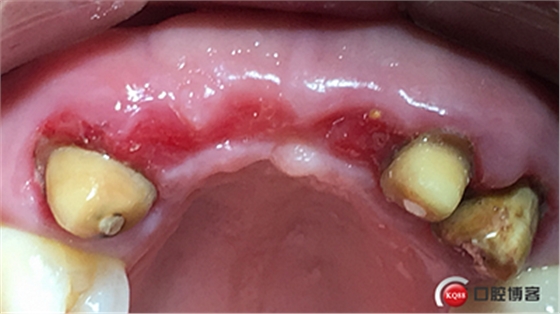

水平切口,鄰牙冠延長。

擴孔,檢查方向。

大家注意這個動作,雖然不翻瓣,但要將唇側(cè)倒凹處骨膜剝離。

植入植體。

將骨粉塞入剝離的骨膜下間隙里既唇側(cè)倒凹處,盡量塞滿。